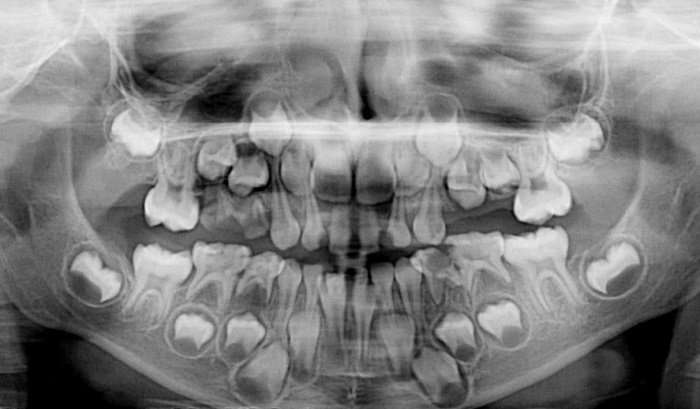

2. Իմաստության ատամներ

Ըստ վիճակագրության՝ շատ երեխաներ այսօր ծնվում են առանց իմաստության ատամների տեղերի:

Նախկինում, երբ մարդը կոշտ սնունդ էր ուտում, ծնոտը զգալիորեն ավելի մեծ էր, իմաստության ատամներն անհրաժեշտ էին, օգնում էին սնունդը լավ ծամել:

Իսկ հիմա, երբ սնունդը ենթարկվում է ջերմային մշակման, իսկ ծնոտը փոքրացել է, իմաստության ատամներին տեղը չի բավարարում ատամնաշարում:

Դրանք տարբեր կերպ են աճում՝ խանգարելով բերանի խոռոչի ընդհանուր հիգիենային: